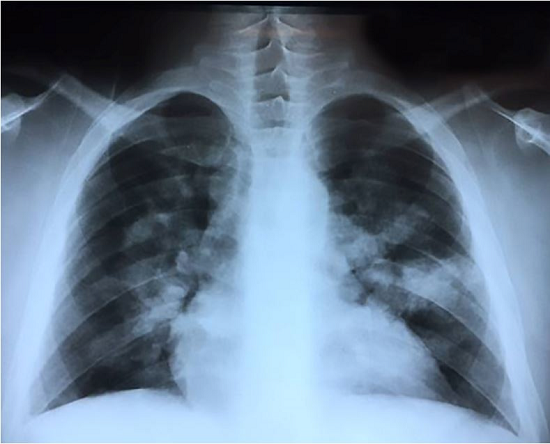

A 36-year-old mulatto male patient sought the emergency facility complaining of lumbar pain of progressive intensity over the past 3 days that worsened with trunk movement. This symptom irradiated to the dorsum and was accompanied by breathlessness. Concomitantly, he complained of wheezing, a cough with mucoid sputum, which was soon followed by dark urine. He had known diagnosis of SCD since the age of 23 years when he experienced an episode of priapism that required surgical intervention. Since then he had not followed any medical treatment. However, he experienced repeated episodes of bone pain, for which he used over-the-counter painkillers as self-medication. He ignored the same diagnosis among his relatives. He smoked for 2 years in his youth and still consumed alcoholic beverages. On physical examination, he was slightly pale, non-icteric and afebrile. His pulse rate was 124 beats per minute, blood pressure 110/80 mmHg, respiratory rate 28 respiratory movements per minute (rmpm), and room air oximetry was 83%. His body mass index was 25. No edema or lymphadenopathy were found. The heart and lungs examination was unremarkable; however, the abdomen was diffusely tender and the liver was palpable 2 cm below the right costal margin. The examination of his back and lumbar region was normal. The laboratory work-up disclosed normocytic normochromic anemia with a hemoglobin of 10.9 g/dL (reference value [RV]: 12.3-15.3 g/dL); hematocrit of 30.1% (RV: 36-45%); red cell distribution width of 20.6% (RV: 14%); leukocytosis with the presence of myelocytes and metamyelocytes in the peripheral blood; and a normal platelet count. The peripheral blood film revealed the presence of poikilocytosis, target cells, and stomatocytes; rare erythrocytes showed the presence of Howell-Jolly bodies, 20 polychromatic, 19 orthochromatic erythroblasts per 100 leukocytes and occasional sickled erythrocytes. Reticulocyte count was not available. C-reactive protein was 173 mg/L (RV: <5 mg/L), lactate dehydrogenase 686 U/L (RV: <250 U/L), and a total bilirubin 1.49 mg/dL (RV: <1.2 mg/dL) at the expense of indirect bilirubin. The renal function tests, electrolytes, liver enzymes, and urinalysis were normal. Blood and urine cultures were negative. The chest x-ray and computed tomography (CT) revealed peri-hilar bilateral confluent ground-glass opacities rendering small consolidations (Figures 1 and 2). An apparently calcified spleen of reduced dimension was an additional finding.

Chest radiography usually reveals unspecific diffuse or patchy bilateral opacities.23 In contrast, chest CT may be useful to evaluate the patients with the potential diagnosis of FES, and, more importantly, to rule out or demonstrate an alternative diagnosis. The most common finding on the CT is the patchy ground-glass opacities, which are usually associated with interlobular septal thickening (crazy-paving pattern), and eventually airspace consolidation and small centrilobular nodules.27

Our patient presented with abdominal and lumbar pain, hypoxemia, and bilateral lung opacities, and a history of sickle cell disease, which led to the diagnosis of vaso-occlusive crisis and acute chest syndrome (ACS). This clinical presentation fulfilled the criteria for ACS, since there was a new radiographic pulmonary infiltrate associated with hypoxemia, tachypnea, cough, and wheezing.33 Fat embolism is one of the proposed underlying mechanisms of ACS.34 Our patient had neither petechial rash nor central nervous system depression prior to his cardiac arrest. The diagnosis of FES was not made ante-mortem possibly because of the lack of its clinical hallmarks and its resemblance with ACS. The chest imaging also led to a diagnosis of a possible lung infection. Moreover, FES is a rare event in non-traumatic patients, whereas ACS is a frequent diagnosis in Brazilian emergency rooms.